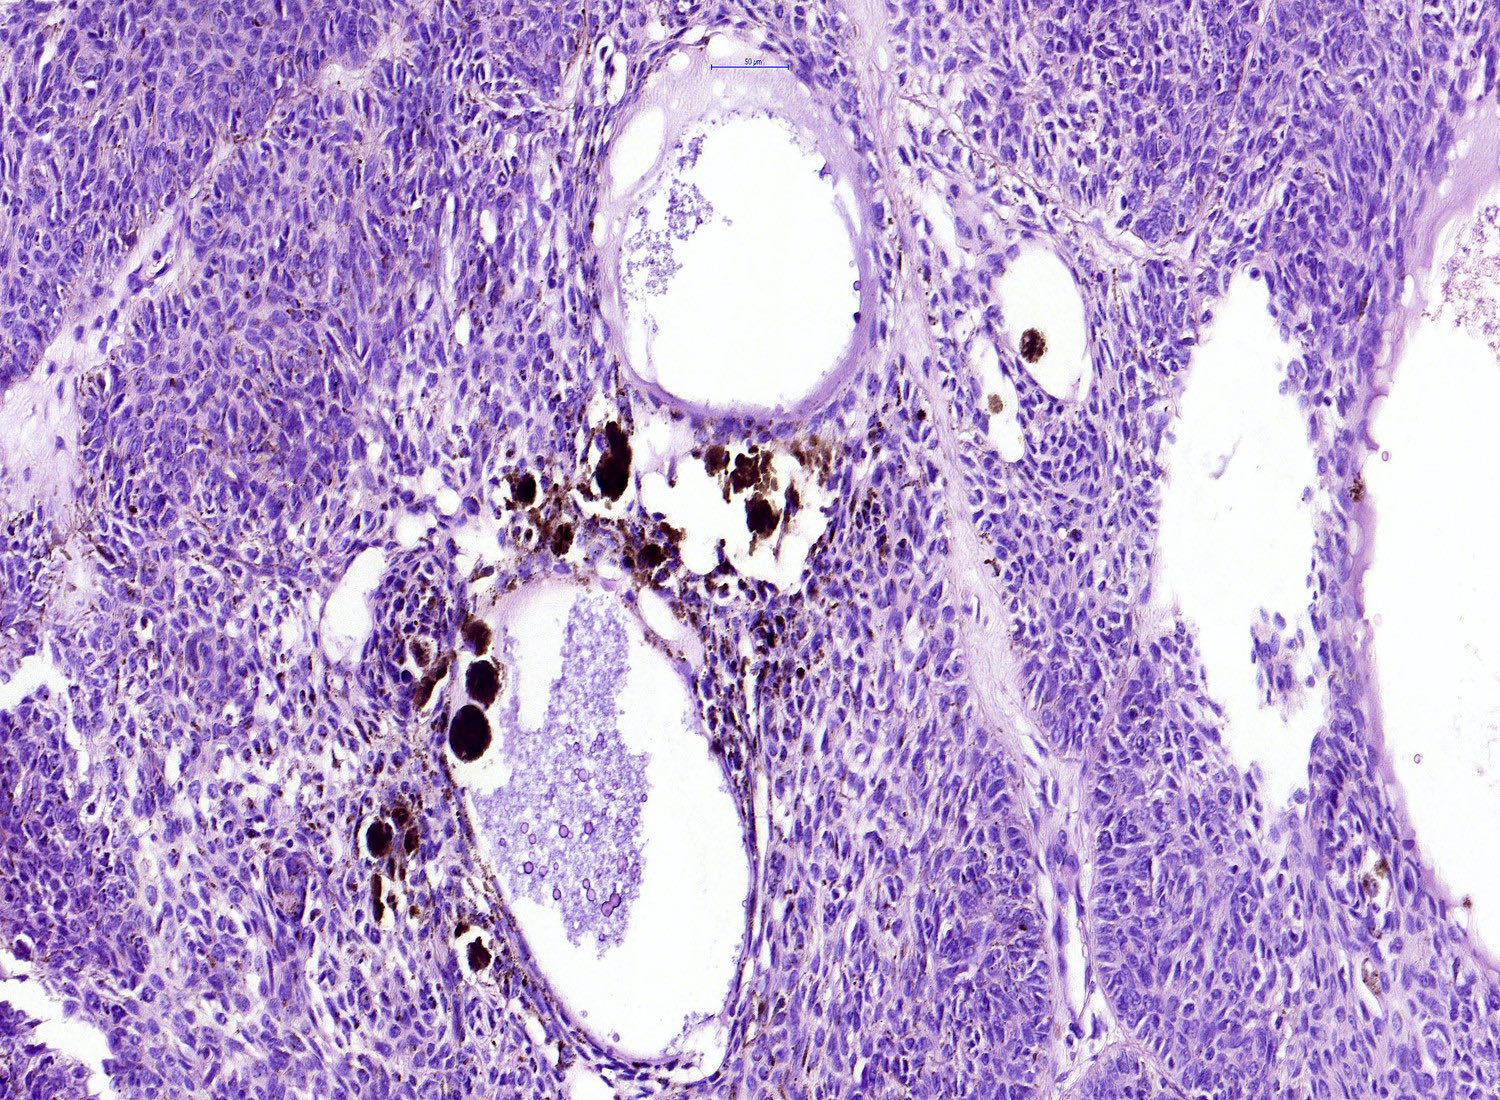

Common variants (Calonje: McKee's Pathology of the Skin, 5th Edition, 2019)

- Keratotic BCC

- Horn cyst formation

- Pigmented BCC

- Nodular and superficial variants can be pigmented

- Colonization of tumor's complexes with melanocytes

- Stromal melanophages

- BCC, fibroepitheliomatous type (fibroepithelioma of Pinkus)

- Anastomosing strands and cords of basaloid cells connected to the epidermis

- Peripheral nuclear palisading with a formation of follicular germ-like structures

- Rarely, isthmic differentiation is present

- Fibrotic stroma that can differentiate towards follicular papillae in the areas of germ-like structure formation

Microscopic (histologic) images

Contributed by Antonina Kalmykova, M.D., Phillip H. McKee, M.D., Sate Hamza, M.D., Eduardo Calonje, M.D.,

Wayne Grayson, M.B.Ch.B., Ph.D., James Sampson, M.B.B.S., M.Sc. and Assia Bassarova, M.D., Ph.D.